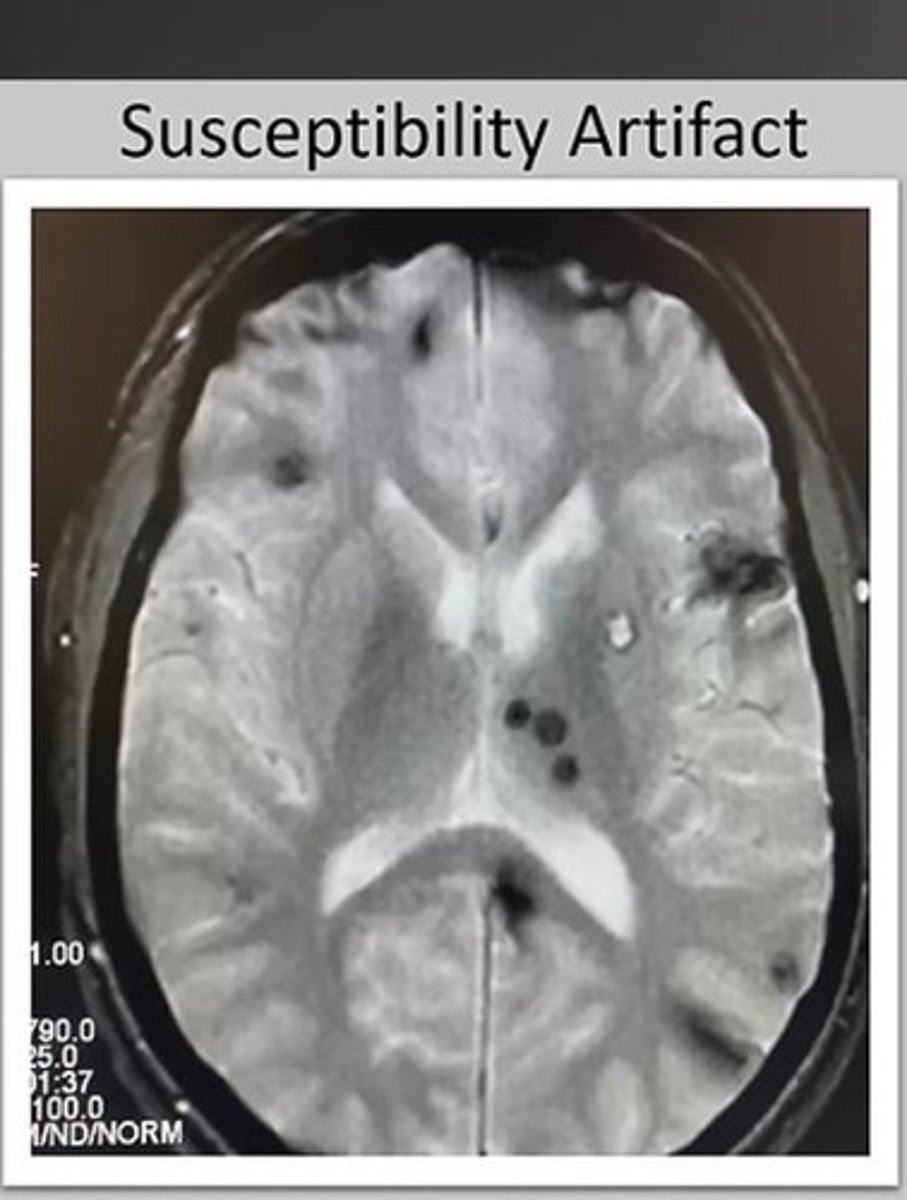

What types of artifacts can occur in MRI?

Small variations in the magnetic field within the field of view (FOV) being scanned, affected by factors like dental work or surgical clips.

What is magnetic susceptibility?

The tendency of some tissues to either attract or repel the magnetic field, leading to differences in signal.

What happens when brain tissue and blood are adjacent in an MRI?

Differences in magnetic susceptibility occur, causing variations in the signal due to the contrasting properties of the tissues.